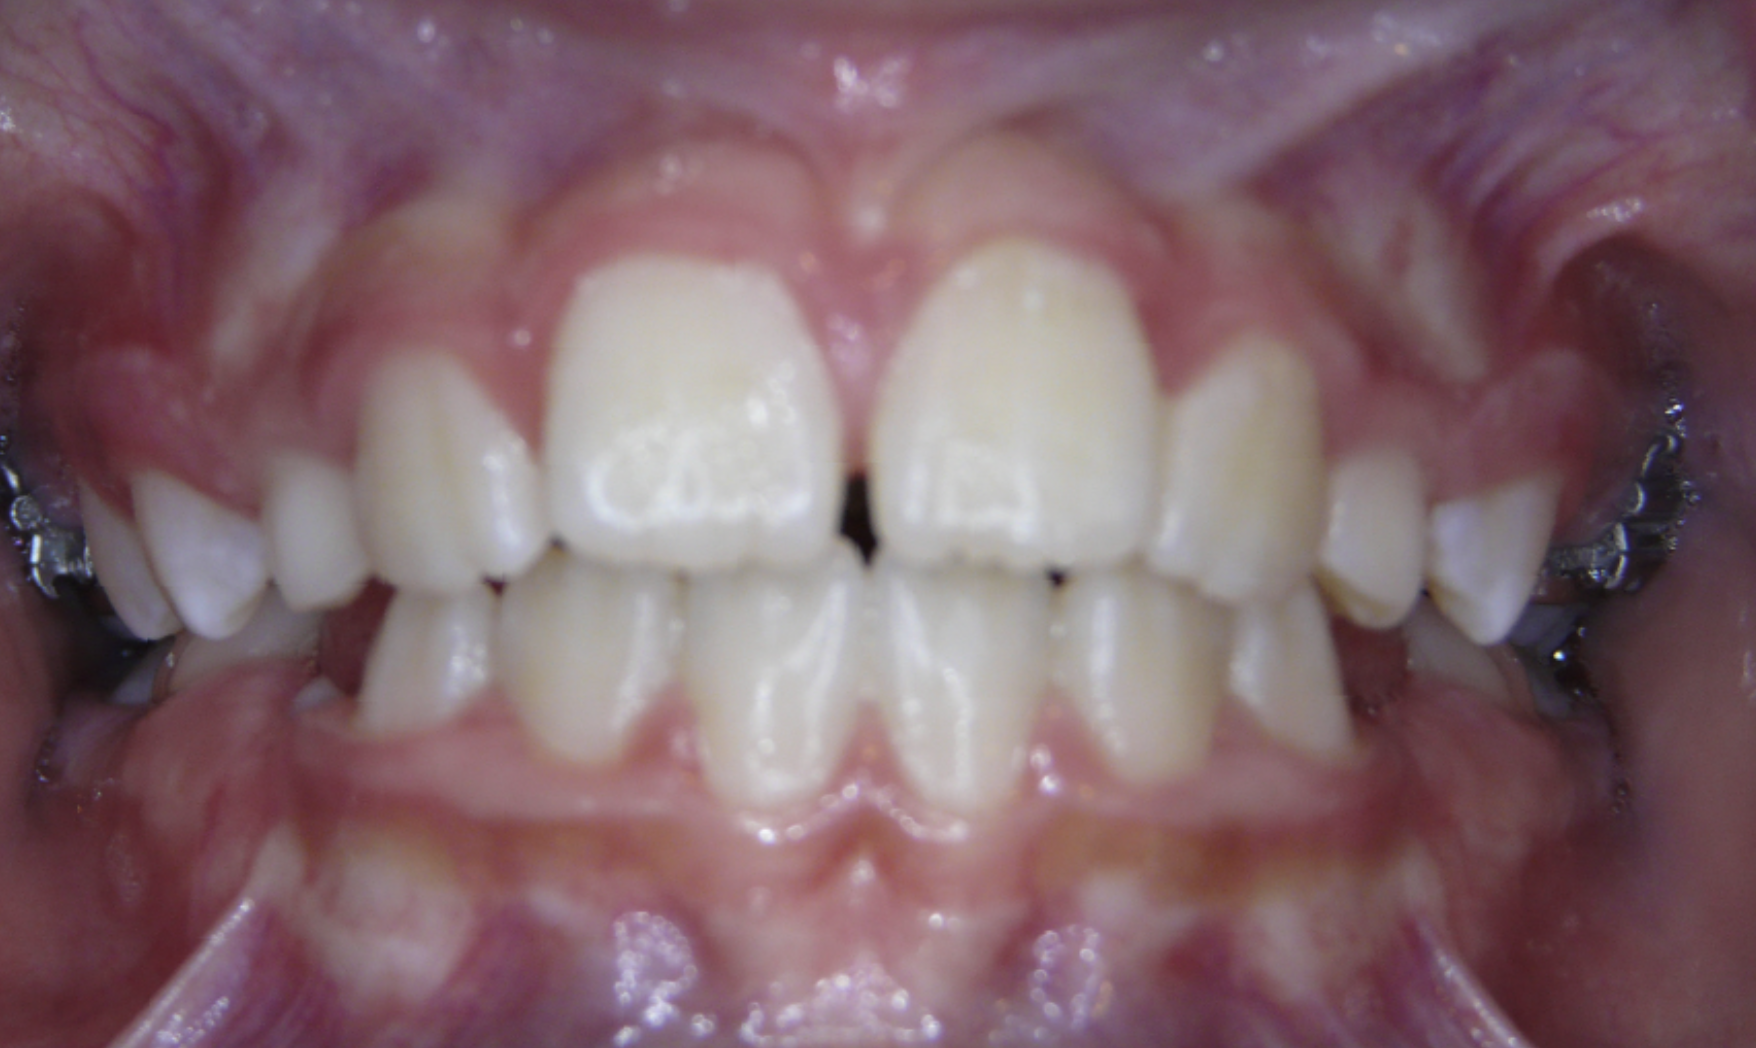

Diastema

Gaps between teeth